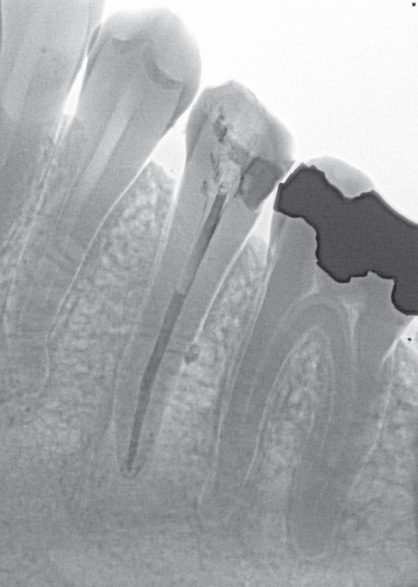

If I'm doing a root canal, the inversion function is especially helpful (see pictures, at right). Sometimes, the apex of the tooth is not easy to define on a multirooted tooth, so in those cases I use the “invert” tool with a trial gutta-percha, which makes it easier to see.

Dr. Mahallati inverts his Schick 33 images to offer greater definition.